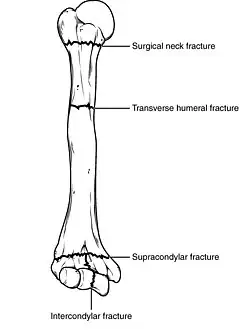

Fractures of the humerus are classified based on the location of the fracture and then by the type of fracture. There are three locations that humerus fractures occur: at the proximal location, which is the top of the humerus near the shoulder, in the middle, which is at the shaft of the humerus, and the distal location, which is the bottom of the humerus near the elbow.[9] Proximal fractures are classified into one of four types of fractures based on the displacement of the greater tubercle, the lesser tubercle, the surgical neck, and the anatomical neck, which are the four parts of the proximal humerus, with fracture displacement being defined as at least one centimeter of separation or an angulation greater than 45 degrees. One-part fractures involve no displacement of any parts of the humerus, two-part fractures have one part displaced relative to the other three; three-part fractures have two displaced fragments, and four-part fractures have all fragments displaced from each other.[13][14][3] Fractures of the humerus shaft are subdivided into transverse fractures, spiral fractures, "butterfly" fractures, which are a combination of transverse and spiral fractures, and pathological fractures, which are fractures caused by medical conditions.[12] Distal fractures are split between supracondylar fractures, which are transverse fractures above the two condyles at the bottom of the humerus, and intercondylar fractures, which involve a T- or Y-shaped fracture that splits the condyles.[7]

A transverse fracture of the humerus shaft -

A spiral fracture of the distal one-third of the humerus shaft -

A displaced supracondylar fracture in a child